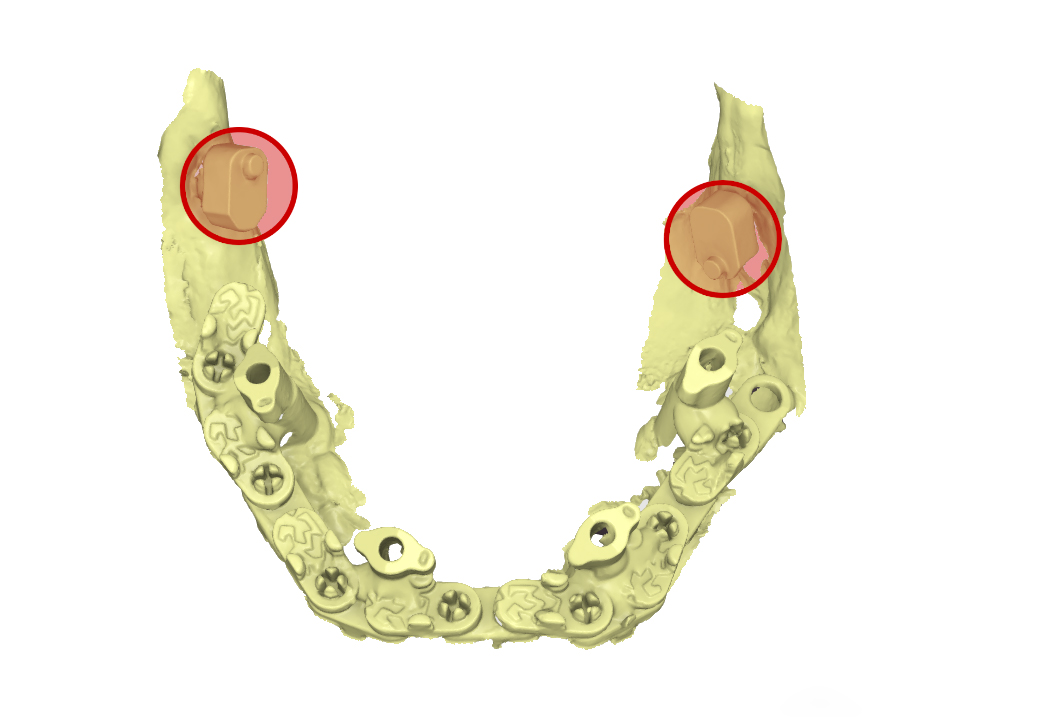

A questo punto inizia la sessione chirurgica vera e propria in cui, rimossa la protesi mobile inferiore, si posizionano 4 impianti dentali (in questo caso in chirurgia orientata) sui quali vengono avvitati i MUA. Durante l’intero atto chirurgico, gli ScanSke rimangono nei settori posteriori della bocca e saranno proprio questi a fornire l’informazione necessaria per poter costruire la nuova protesi fissa su impianti nel corretto spazio inter-arcata della paziente (Fig.6). Eseguita la sutura, si posizionano gli scanbody implantari e si esegue una scansione post-chirurgica che rileva sia gli ScanSke che gli scanbody implantari appena inseriti. Per migliorare l’accuratezza della scansione e facilitare il flusso di scansione in una cresta edentula sanguinante, gli scanbody implantari vengono solidarizzati mediante una dima di scansione (Fig. 7 a, b). Per fornire al laboratorio ulteriori informazioni, viene anche eseguita una successiva scansione della mucosa su cui poggerà la nuova protesi (Fig. 7c). Grazie alle scansioni rilevate, sia quella pre-chirurgica che quelle post chirurgiche, con gli ScanSke sempre fissi e immutati nella loro posizione, il tecnico di laboratorio riceve in remoto i files .stl delle tre scansioni intraorali, ed esegue la sovrapposizione delle stesse, ritrovandosi nell’articolatore digitale le arcate dentali nel corretto rapporto spaziale (Fig. 8), ottenuto grazie alla posizione immutata degli ScanSke e nello spazio protesico così ottenuto, progetta e realizza (in flusso 100% CAD/CAM) la protesi fissa nel rispetto dell’occlusione abituale della paziente (Fig. 9, 10, 11).

file .stl della sovrapposizione delle tre scansioni

Fig. 8. (a) file .stl della sovrapposizione delle tre scansioni, in evidenza gli ScanSke

Arcate scansionate all’interno dell’articolatore digitale

Fig. 8. (b) Arcate scansionate all’interno dell’articolatore digitale, in evidenza gli ScanSke.

Prospettiva frontale della protesi progettata

Fig. 9. (a) Prospettiva frontale della protesi progettata in base all’occlusione abituale della paziente

Prospettiva dall’alto della protesi inferiore

Fig. 9. (b) Prospettiva dall’alto della protesi inferiore, in evidenza gli Scan Ske.